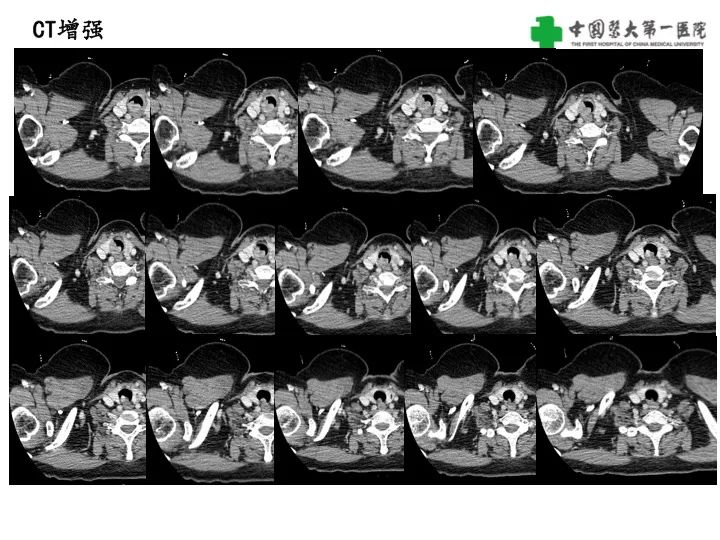

气管腺样囊性癌1例CT影像

【病例】气管腺样囊性癌1例CT影像-1